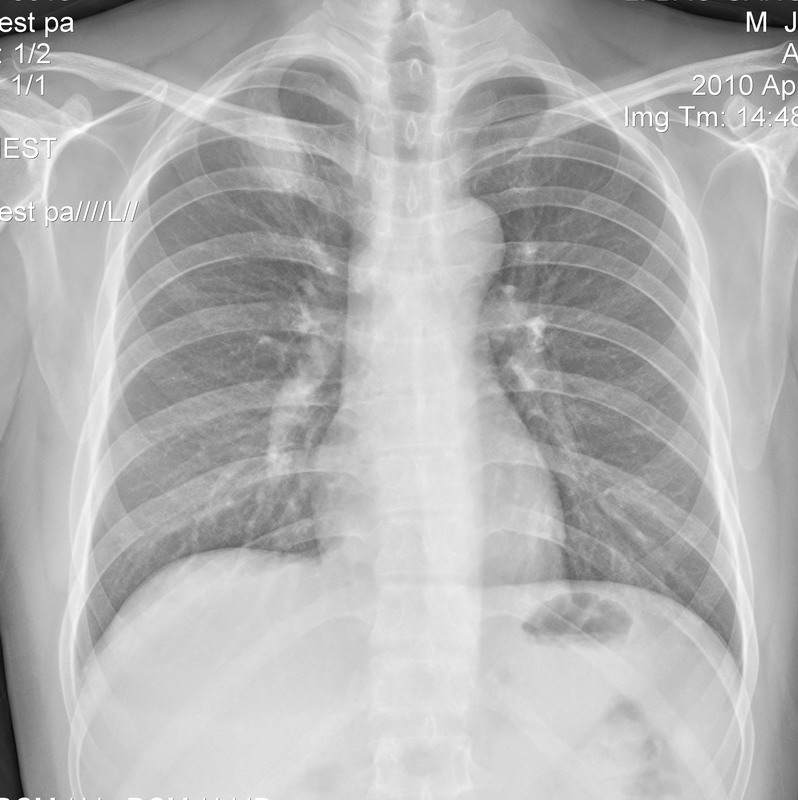

418 男 28 发热三天 右侧扁桃体二度肿大

右上肺结核可能性大,建议ct进一步检查。

右上肺首先考虑结核,不能排除炎症。建议抗炎治疗后复查

首先考虑结核,建议相关实验室检查。

右上肺感染性病变;建议抗炎治疗后复查排除结核。

先考虑肺炎,治疗后复查,排除结核。